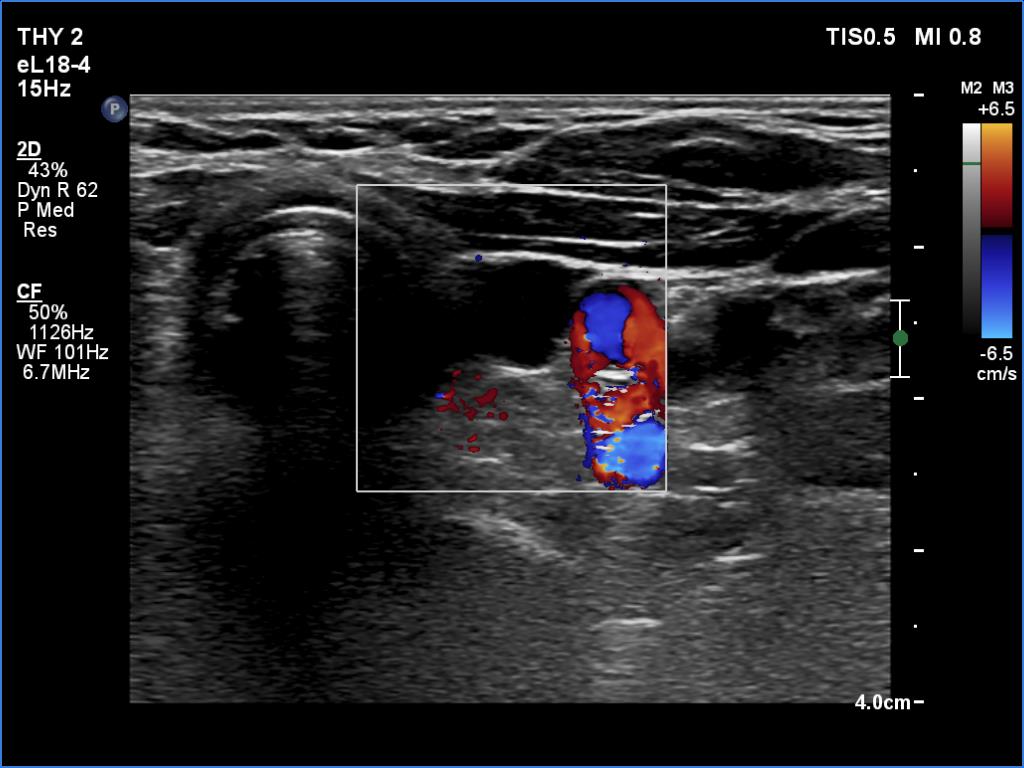

Left lobe, transverse scan, color Doppler mode. The lesion is avascular.